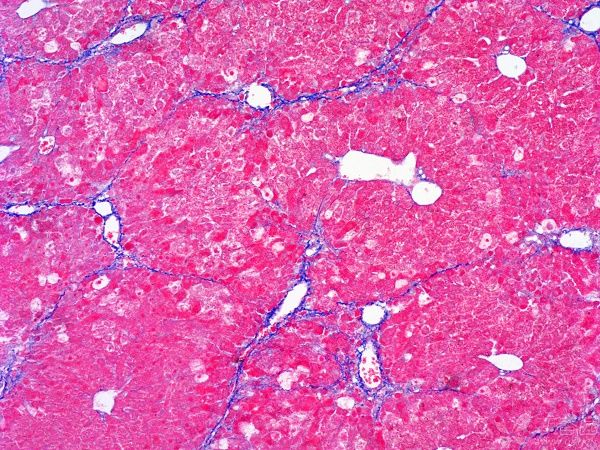

MASSON染色利用不同染料分子與組織結(jié)構(gòu)的相互作用,實(shí)現(xiàn)對膠原纖維和肌纖維的精準(zhǔn)區(qū)分。在染色過程中,肌纖維呈現(xiàn)為紅色,而膠原纖維則呈現(xiàn)為綠色或藍(lán)色。這種色彩對比使得纖維組織在顯微鏡下變得清晰可見,醫(yī)生能夠清晰地觀察到纖維化的程度和范圍。

圖1. Masson組織染色結(jié)果示例(最右列),可看到不同處理?xiàng)l件下膠原纖維(藍(lán)色)和肌纖維(紅色)的分布不同

①正常組織染色結(jié)果

在正常組織中,MASSON染色通常呈現(xiàn)出均勻的藍(lán)色背景,其中肌肉纖維和血管等結(jié)構(gòu)清晰可見。這種染色結(jié)果表明組織結(jié)構(gòu)正常,無明顯的纖維化病變。